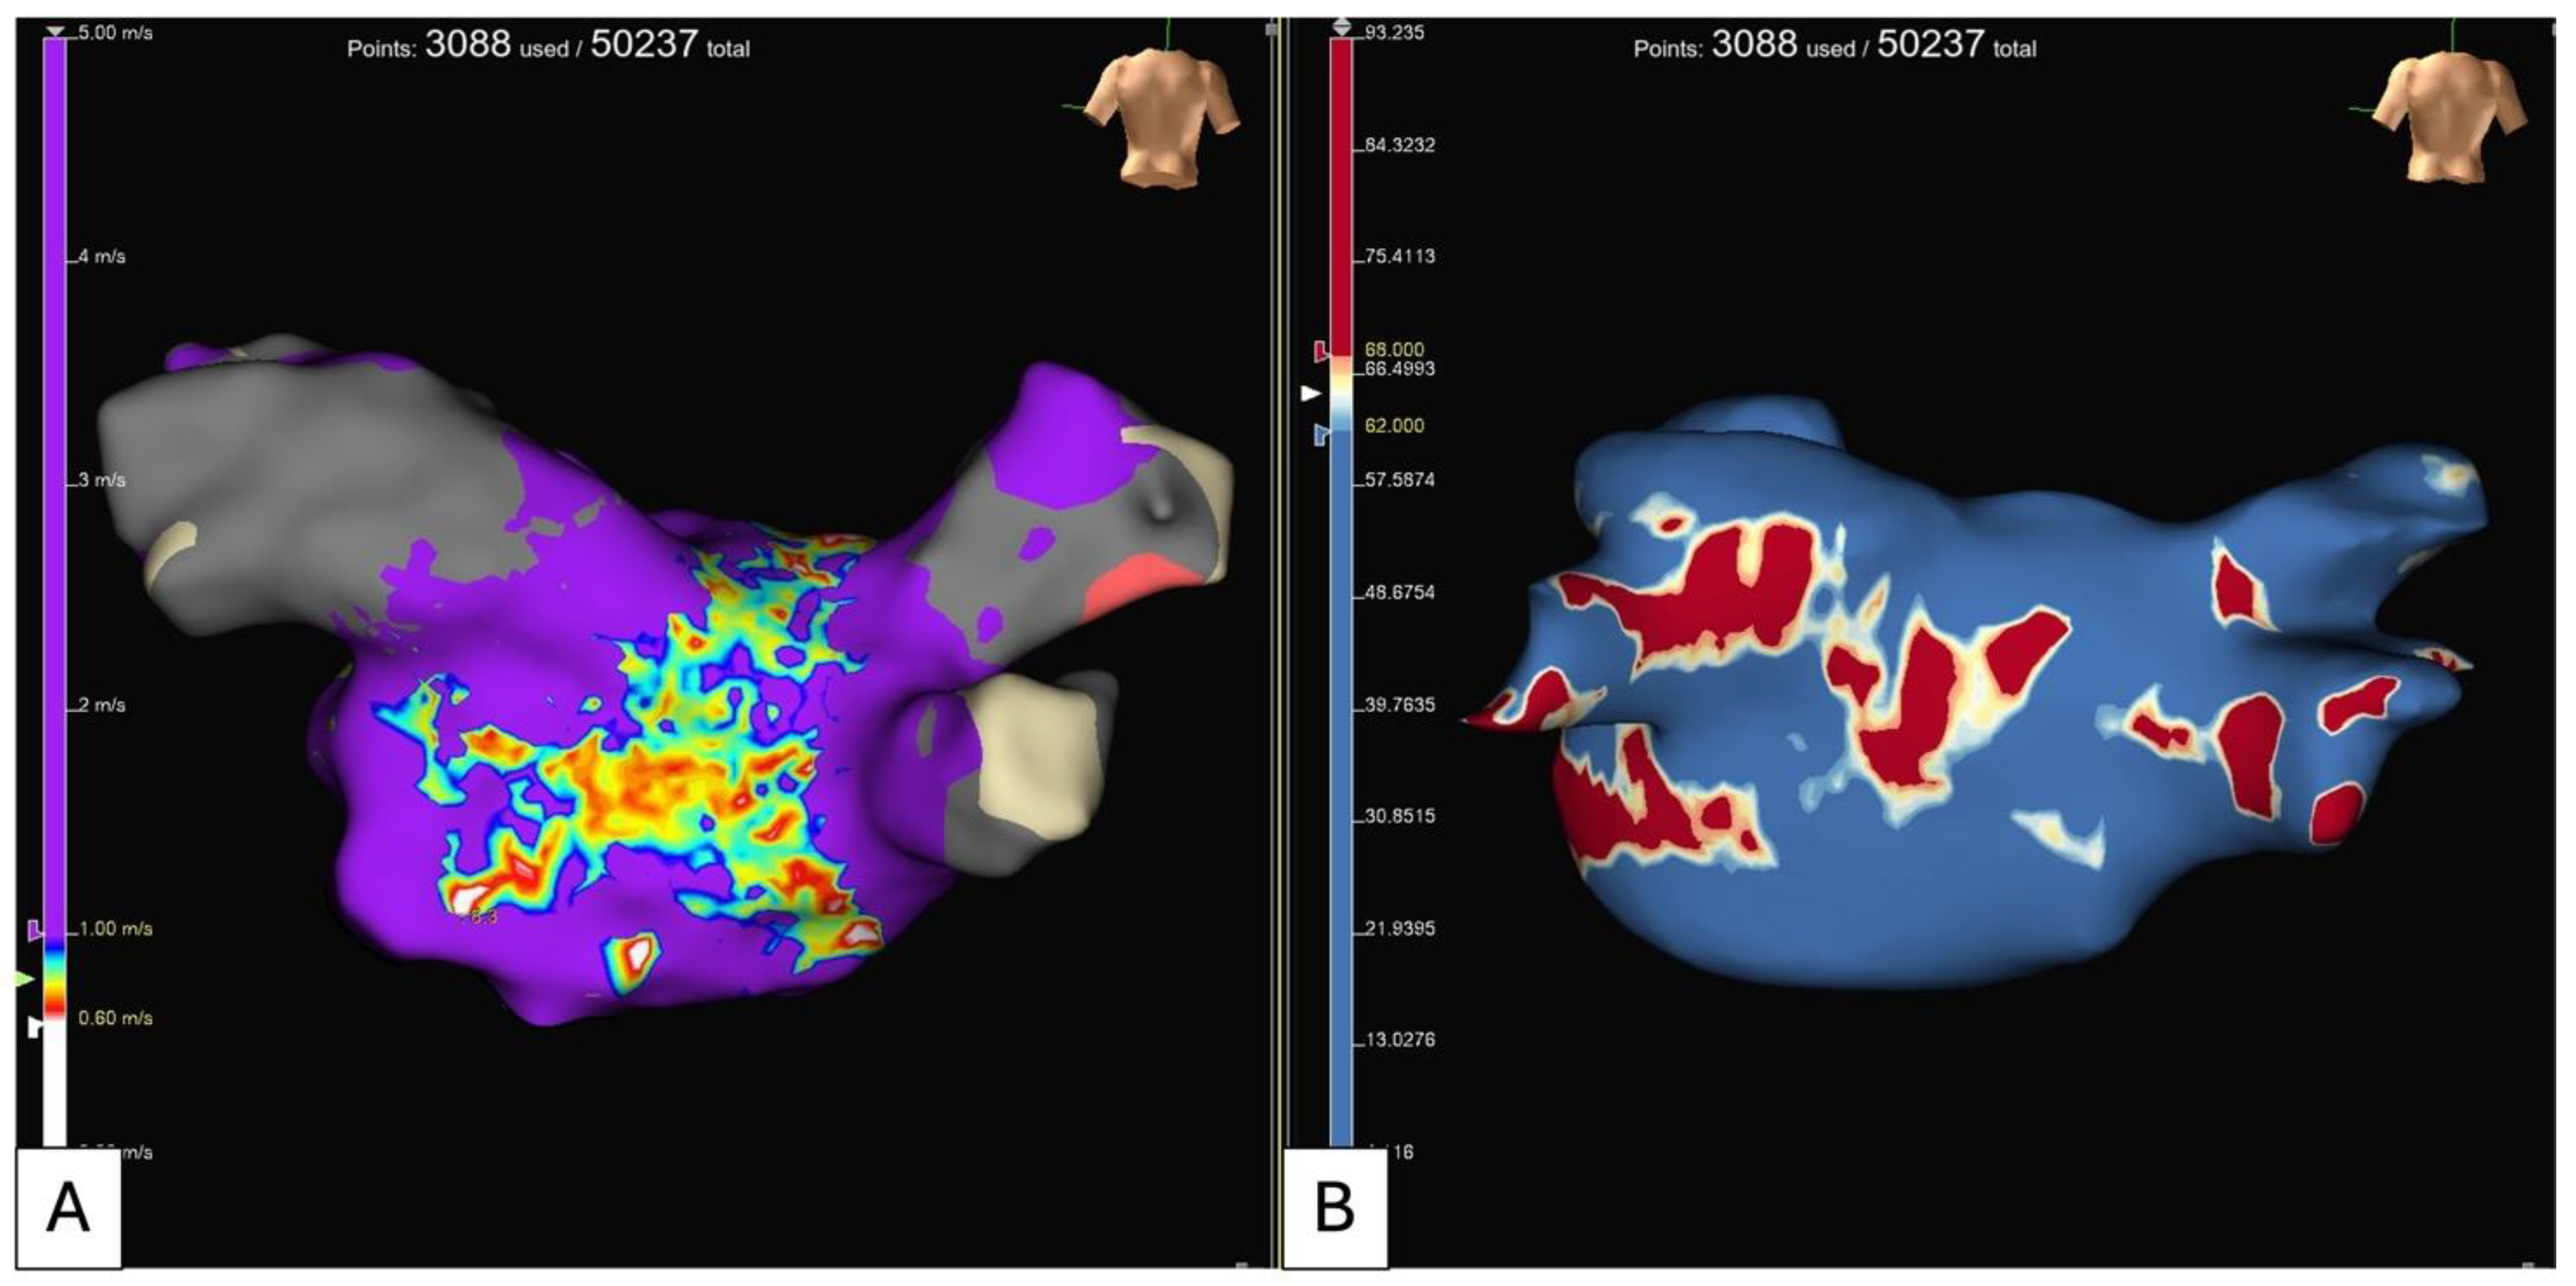

- Rolf, S.; Kircher, S.; Arya, A.; Eitel, C.; Sommer, P.; Richter, S.; Gaspar, T.; Bollmann, A.; Altmann, D.; Piedra, C.; et al. Tailored Atrial Substrate Modification Based on Low-Voltage Areas in Catheter Ablation of Atrial Fibrillation. Circ. Arrhythmia Electrophysiol. 2014, 7, 825–833. [Google Scholar] [CrossRef] [PubMed]

- Li, K.; Xu, C.; Zhu, X.; Wang, X.; Ye, P.; Jiang, W.; Wu, S.; Xu, K.; Li, X.; Wang, Y.; et al. Multi-Centre, Prospective Randomized Comparison of Three Different Substrate Ablation Strategies for Persistent Atrial Fibrillation. Europace 2023, 25, euad090. [Google Scholar] [CrossRef]